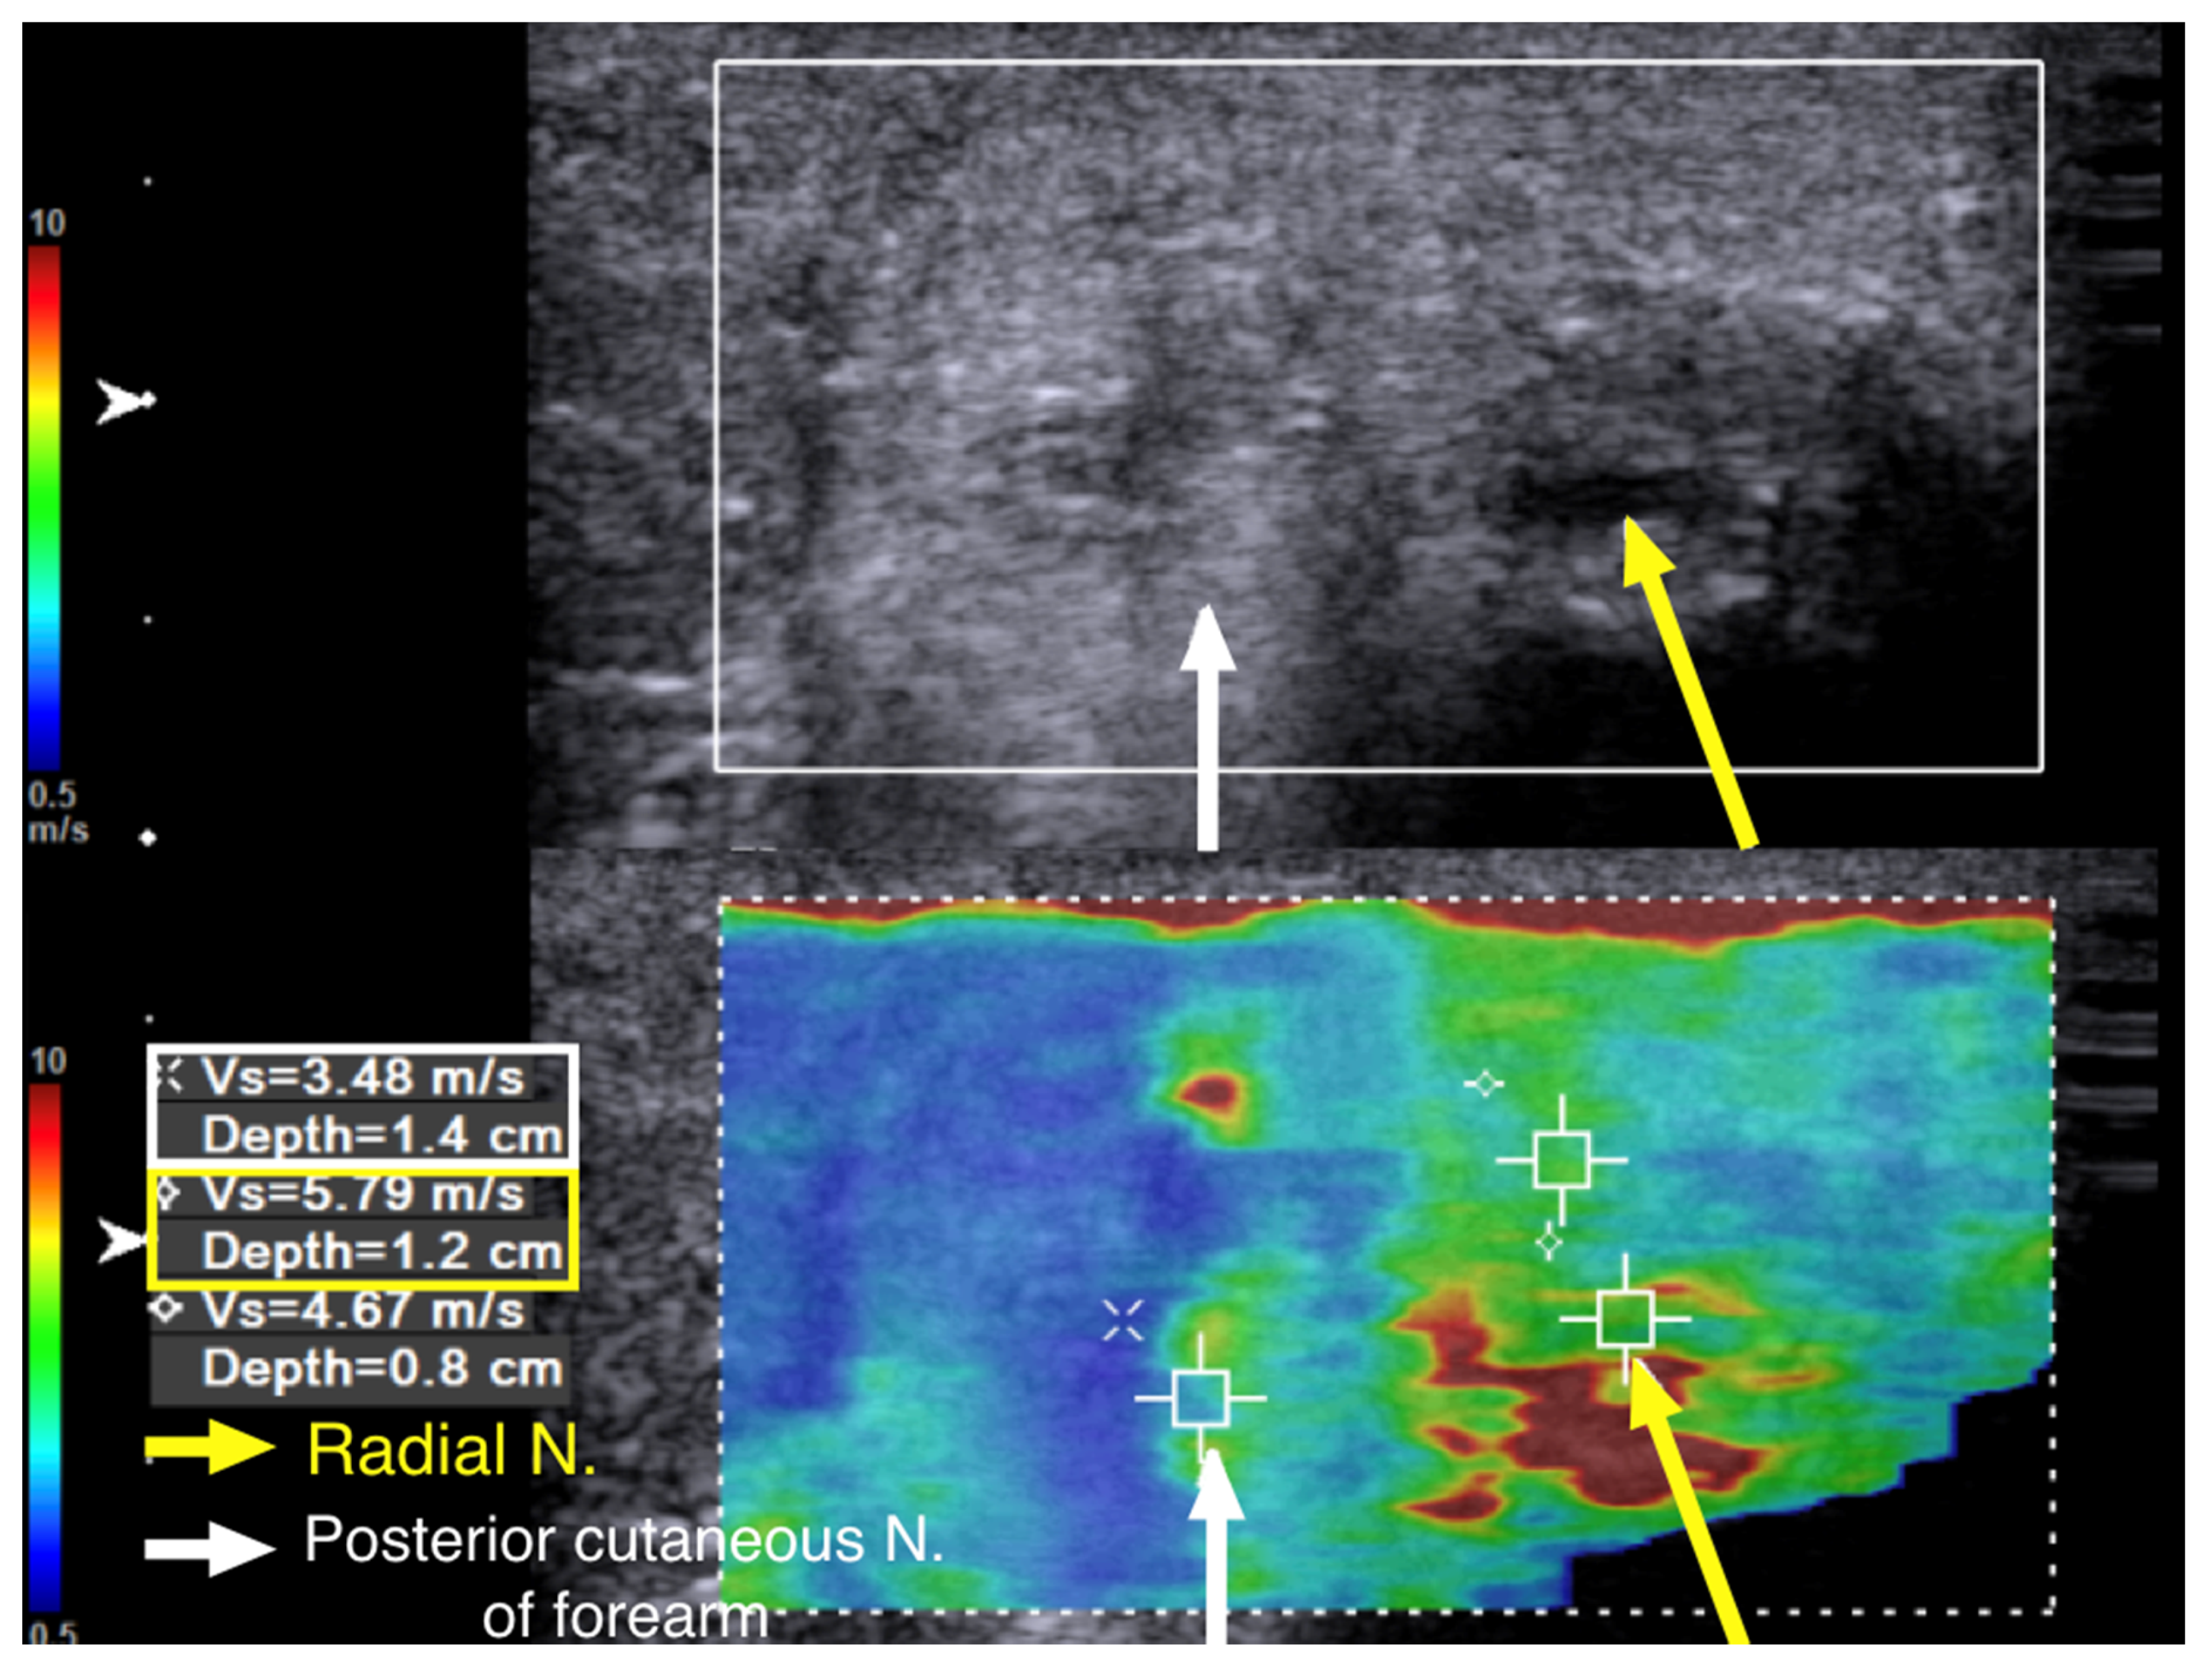

We performed cross-sectional SWE of the radial nerve and its branches along their course from the entrance into the spiral groove to the elbow level. Points of increased hardness, as high as 9.91 m/s, were identified with SWV at the spiral groove level. (Figure 5). Although some of the cross-section views of the radial nerve and the posterior cutaneous nerve of forearm looked swollen and hypoechoic after their respective exits from the spiral groove, there was no increased hardness measured with SWE (Figure 6).

The SWV of the posterior cutaneous nerve of forearm was 3.48 m/s (Figure 6). This indicated that, although the patient had allodynia over the innervation area of the posterior cutaneous nerve of the forearm, the nerve was injured proximal to its exit from the spiral groove. Multiple segments of increased hardness along the radial nerve and its branches were marked with a marker on the skin before we performed ultrasound-guided hydrodissection (Figure 7a). Five to ten cubic centimeters of D5W were used in each of the mark-up segments, which added up to a total of 60 cc of D5W to dissect the adhered scar tissues around the nerves.

Traditionally, when using US to identify entrapment sites, we either look for sudden changes in the CSA of the nerve, the notch sign, any enlarged fascicles, hypoechoic changes in the fascicles, and hyperechoic signals surrounding the nerve, or we try to reproduce symptoms with sonopalpation [2,5]. However, we must be aware that scar tissue can grow in several areas along the course of a nerve, causing multiple entrapments. The distorted anatomy of the tissue/neural architecture after the operation makes identification of precise scar tissues surrounding the nerve difficult with conventional US. As in our second patient, scar tissue may encroach upon the nerve from the bone, causing adhesion (Figure 6), and the hyperechoic bony cortex makes identification of the precise location of the scar with conventional US techniques more difficult.

Figure 6. Case 2: Shear wave velocity at the exit of the spiral groove. A 43-year-old man with radial nerve palsy after plating of a left humeral shaft fracture. Ultrasound images with cross-sectional view of the radial nerve after its exit from the spiral groove. The radial nerve and the posterior cutaneous nerve of the forearm were swollen. The shear wave velocity of the radial nerve was 5.79 m/s (yellow arrow and box), and that of the posterior cutaneous nerve of the forearm was 3.48 m/s (white arrow and box).